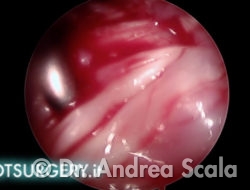

L’asportazione della sporgenza calcaneare crea una cavità in prossimità della inserzione del tendine d’achille. La telecamera ruota verso il “soffitto” della cavità per esaminare il tendine d’achille. I residui della borsa infiammata aderiscono alle fibre del tendine.

L’uncino palpatore valuta la consistenza e la tensione delle fibre del tendine.